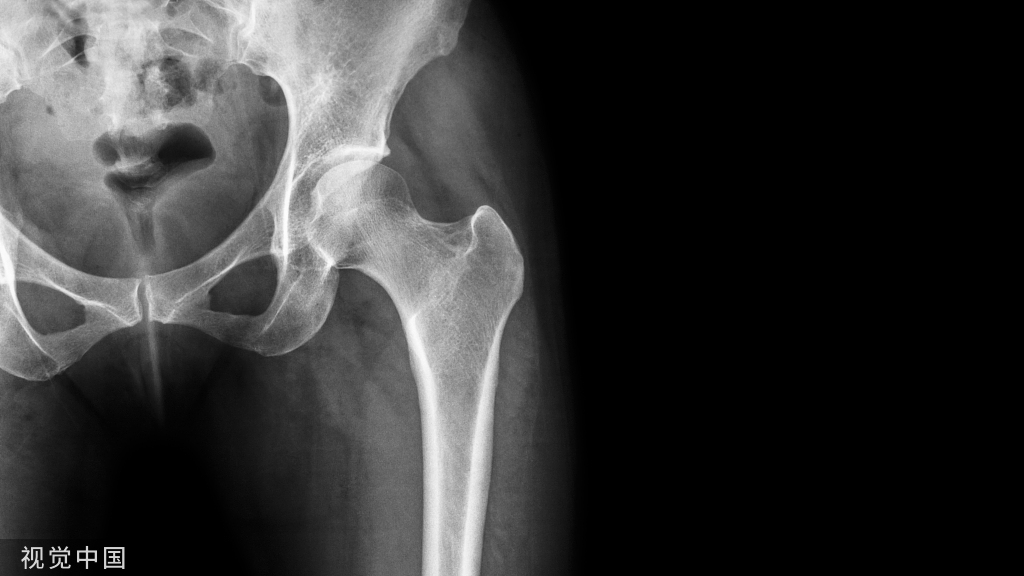

髋关节手术,对于大多数骨科医生来说都是复杂和高深的,因为他位置深在,结构复杂,今天我们就重点来学习髋关节的解剖和手术入路,值得学习借鉴!